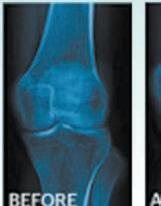

Dr. Angelina Alejandro, NMD (Naturopathic Physician)

Join us for a FREE GOURMET DINNER Seminar with leading Natural Medicine and Wellness Expert, Dr. Angelina Alejandro, NMD (Naturopathic Physician)

Dr. Alejandro will tell you about the latest methods, breakthroughs and time-tested strategies that will help you permanently and safely remove unwanted weight while quickly reclaiming your health, your youth and your life!

✔ Learn how Hormone Imbalances - man or woman - can distort your midsection into a large belly and prevent weight loss, even with dieting and exercise.

✔ Understand why “Counting Calories” doesn’t work, and the biggest mistakes people make with exercise that prevents weight loss.

✔ Clear approaches that inspire, are compatible with full lifestyles, and which show quick results with long-term success.

✔ Discover what really works for permanent loss of bulges and belly fat, safely and healthfully!

SEMINAR DATE: THURSDAY, MARCH 2ND 2017

418-2653 CANTINA LAREDO 7361 E. Frank Lloyd Wright Blvd. Scottsdale, AZ 85260

✔ Understand why prevention is key, what is necessary for “ageless” living well into our “senior” years. (NOW is the time!) Call